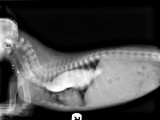

Bonjour,

Je connais malheureusement le problème du méga car mon chien a été diagnostiqué à la naissance. les symptomes sont des régurgitations, et amaigrissement. Le diagnostic se fait avec une radio toute bête, en cinq minutes vous serez fixée. Ce problème ne se guérit pas mais le chien peut tant bien que mal vivre avec son méga plusieurs années. Le mien est fragile et très maigre j'ai peur de ne pas pouvoir le garder très longtemps surtout qu'il n'y a pas grand chose à faire. Le lien qui vous est donné sur le méga est très documenté. Bon courage |